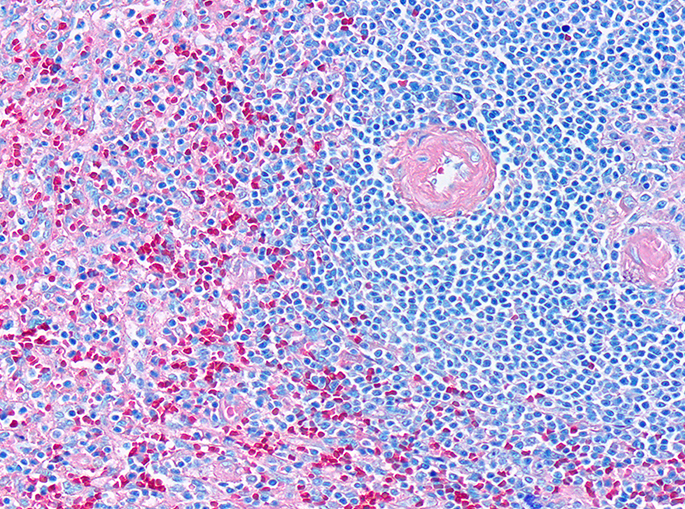

BAZO

Órgano linfoide 2° (secundario)

Encapsulado, carece de corteza y médula. Se encarga de eliminar células senescentes.

Pulpa blanca: nódulos linfáticos + PALS.

Pulpa roja:encargada de filtrar la sangre + Cordones de Billroth.

El bazo es un órgano encapsulado encargado de la eliminación de células senescentes, entre ellas los eritrocitos.Observe que el bazo carece de corteza y médula. Se organiza en pulpa blanca y pulpa roja.Se observa la cápsula de TCDi en contacto con la luz y la organización del bazo.Identifique las arteriolas centrales características de los nódulos linfáticos en el bazo.Arteriola central, Bazo, HyE.Las Vainas Linfáticas Periarteriolares (PALS) son cúmulos del Linfocitos T que rodean la arteriola central.La pulpa esplécnica nos permite identificar la organización del bazo, esta se divide en blanca y roja.Observe el nódulo linfático secundario, con su centro germinal, su zona del manto y una arteriola central.Bazo, HyE.Bazo, HyE.Bazo, Tinción de Giemsa.La arteriola central no siempre es «central», recuerda que puede ser desplazada por los linfocitos presentes en el nódulo linfático.Con impregnaciones argénticas podemos observar fibras reticulares (Colágena III)Delimitado con la línea negra podemos observar un nódulo linfoide secundario y señalado con la flecha negra observamos una arteriola central.Identifique.Identifique la arteriola central. Bazo, Tinción de Giemsa.Bazo de ratón, HyE.Identifique en la parte superior de la fotomicrografía la cápsula del bazo.